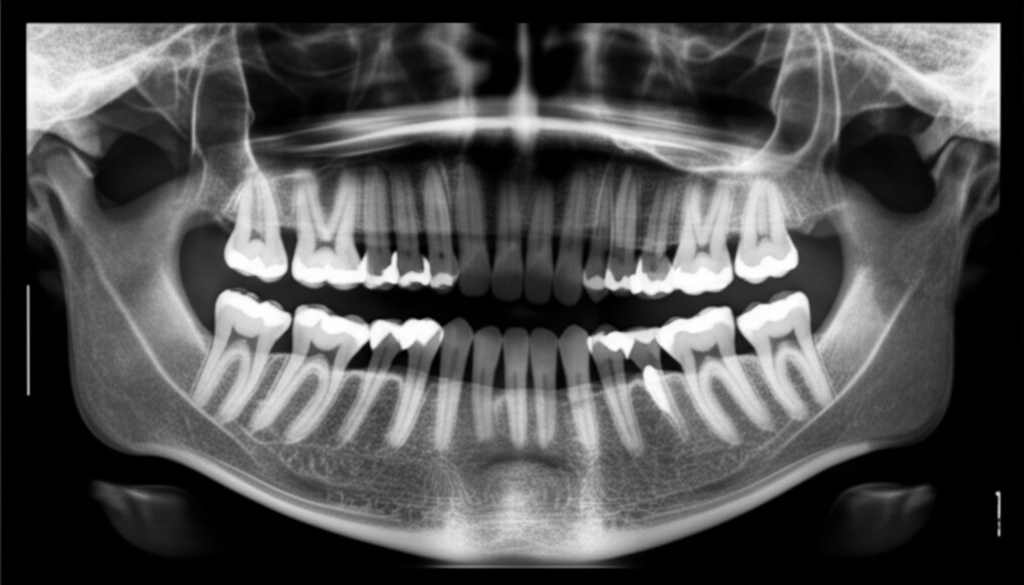

사랑니는 보통 10대 후반에서 20대 초반에 자라나는 어금니입니다. 모든 사람에게 사랑니가 나는 것은 아니며, 나는 경우에도 올바르게 자라지 못하고 잇몸 속에 매복되어 있거나 비스듬히 자라는 경우가 많습니다. 이렇게 비정상적으로 자라는 사랑니는 다양한 문제를 일으킬 수 있어 발치가 권장됩니다.

- 치아 배열 불균형: 사랑니가 비스듬히 자라면서 다른 치아를 압박하여 치열을 불균형하게 만들 수 있습니다. 이는 부정교합을 심화시키고, 심미적인 문제로 이어질 수 있습니다.

- 방사선 촬영비: X-ray 또는 CT 촬영을 통해 사랑니의 위치와 상태를 파악하는 비용입니다.

- 첨단 장비: 대학병원에서는 CT, 3D 프린팅 등 첨단 장비를 사용하여 사랑니의 위치와 신경과의 관계를 정확하게 파악하고, 수술 계획을 수립합니다. 이는 신경 손상 가능성을 최소화하고, 수술의 성공률을 높이는 데 기여합니다.

- 정확한 진단: 치과에 방문하여 구강 검진 및 방사선 촬영을 통해 사랑니의 상태를 정확하게 진단받아야 합니다. 의사와 충분히 상담하여 발치 여부를 결정하고, 수술 계획을 세워야 합니다.